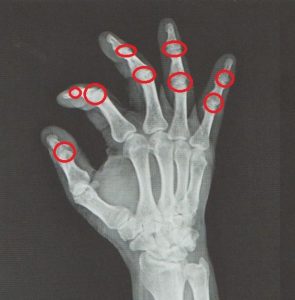

손가락 퇴행성 관절염

손가락 퇴행성 관절염 안녕하세요. 고래한의원 원장 박대명입니다. 오늘은 손가락 퇴행성 관절염에 대해 안내드리겠습니다. ‘손가락 퇴행성 관절염’은 손가락 관절의 활막 조직에 변화가 생기면서 점진적인 퇴행 과정을 거쳐 관절의 형태 변화나 구조적인...